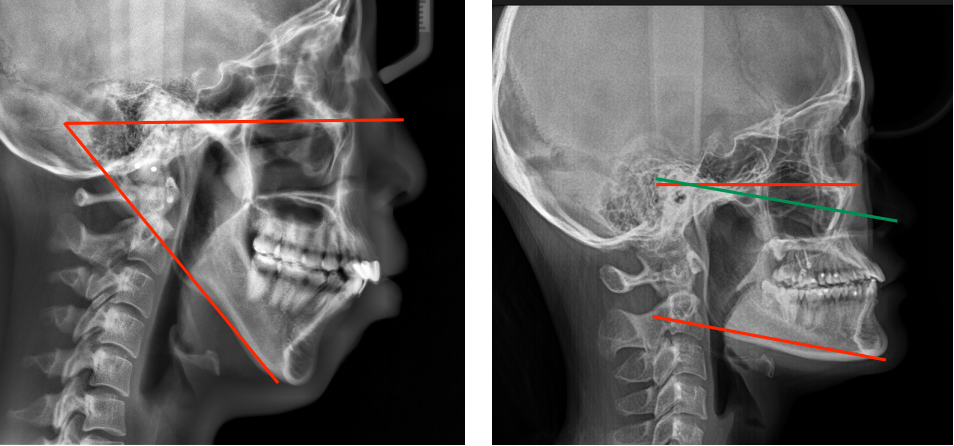

3、改变下颌后部颌平面从倾斜到水平。